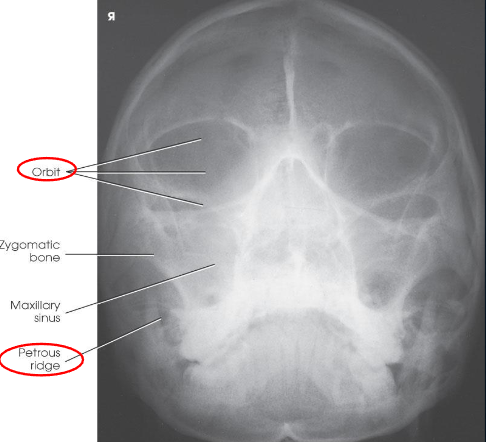

PA/PA axial (Caldwell) skull

PA skull image criteria

evidence of proper collimation

entire cranial perimeter showing three tables of squamous bone

no rotation:

equal distance from lateral borders of skull to lateral border of orbits

symmetric petrous ridges

petrous ridges fill orbits

penetration of frontal bone without excessive density of lateral borders of skull

PA axial (Caldwell) skull image criteria

petrous ridges demonstrated in lower third of orbits